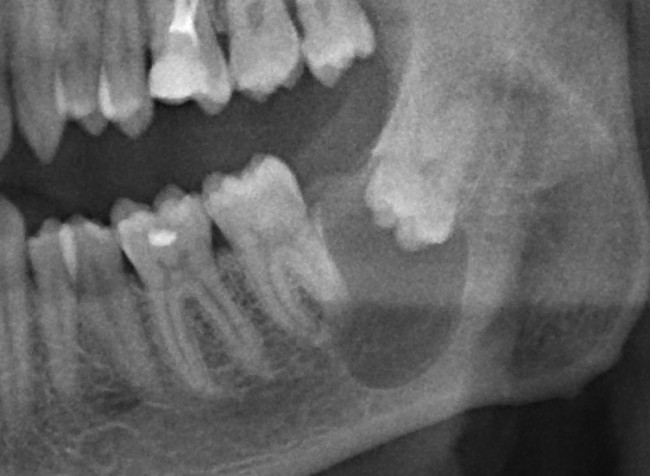

К нам в клинику обратился молодой человек с целью плановой санации: почистить зубной налет, вылечить кариес и т. д. Перед лечением ему сделали панорамный снимок. На снимке вот это:

Напомню, он пришел с целью плановой санации, а это значит, что ни зуб мудрости, ни киста. ни что-то там еще его не беспокоят. А теперь, внимание, вопрос ко всем вам:

— Нужно ли удалять зуб мудрости?

Следуя логике некоторых из моих коллег, а именно «если не беспокоит — не трогать«, этот зуб мудрости и кисту удалять не нужно. Не беспокоит же! Вот когда заболит, тогда придете! Слышали такие рекомендации? Я тоже слышал, причем неоднократно. Причем, от очень «авторитетных» (кавычки неспроста) специалистов.

Однако, если мы так все оставим, то, скорее всего, это приведет вот к такой ситуации, при которой мы всерьез будет рассуждать уже не только об удалении выросшей кисты и зуба, но и о сохранении соседних зубов и части нижней челюсти вообще. Скажет ли пациент «спасибо», когда узнает, что именно наше бездействие привело к таким результатам? Мы, конечно, в ответ можем помахать списком литературы и ссылками на «авторитетные» (кавычки неспроста) источники, но станет ли ему от этого легче? Вряд ли.

Вернусь к нашему клиническому случаю. Да, ни зуб мудрости, ни киста, которая из-за него возникла, нашего пациента не беспокоят. Тем не менее, все вы видите явные показания к удаления и ретинированной восьмерки, и кисты.